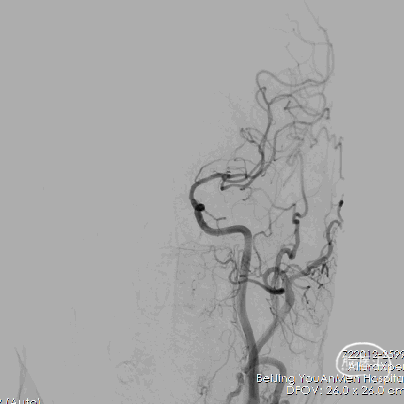

5、双微导管分区填塞动脉瘤。

6、填圈期间动态造影监测左侧大脑前动脉血流有无影响。

7、在瘤颈处可见可疑血栓影。

8、左侧大脑前动脉血流变慢。

9、动脉给予替罗非班后,左侧大脑前动脉血流未见好转。

10、将瘤颈口的微导管撤出后,左侧大脑前动脉血流较前略有好转。

11、反复造影观察后血流速度仍然减慢,造影见少量弹簧圈突入前交通动脉。

12、超选左侧大脑前动脉跟进微管,可见路径迂曲。

13、支架置入后左侧大脑前动脉血流好转。